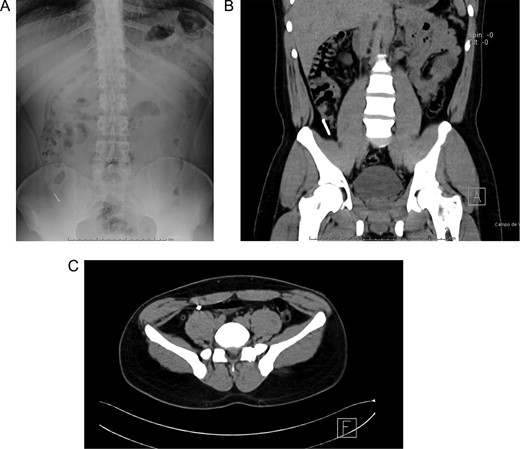

(A) Completely resected appendix. (B) Appendix and metallic nail.

In this context, a surgical approach was needed to assess the appendix and the cecum wall. After a Rocky-Davis incision, the appendix was exposed and an object of hard consistency was found at its tip (Fig. 3B). The surgical decision was straightforward, the appendix was resected, and the surgery was completed without complications (Fig. 1C).

After this, the appendix was dissected and a 30 mm nail was found inside its lumen (Fig. 2C and Supplementary Video).